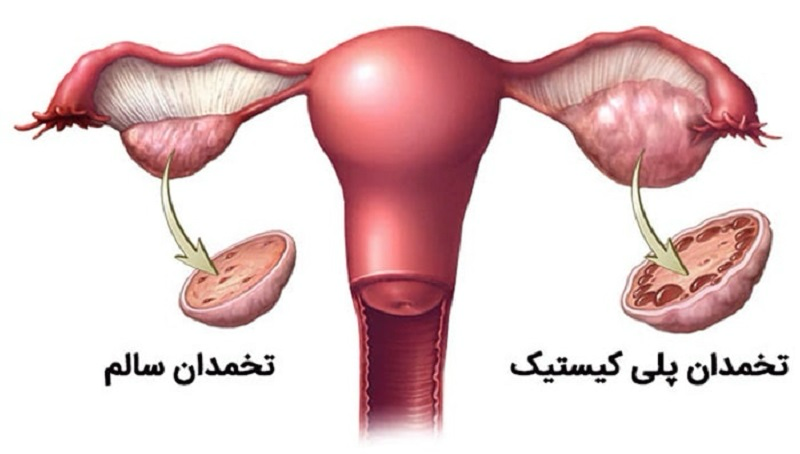

بهترین دکتر سندرم تخمدان پلی کیستیک بندرعباس + لیست 10 تایی